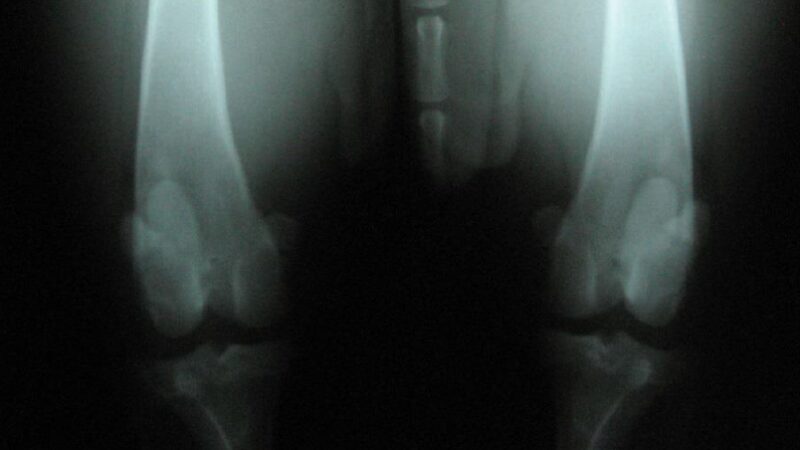

Die Schubladenprüfung erfolgt in Seitenlage bei leicht gebeugtem Knie (ca. 120–140°). Der Femur wird über die Kondylen fixiert, die Tibia am Tibiakopf gefasst und kontrolliert nach kranial verlagert. Entscheidend ist nicht nur das Vorliegen einer Translation, sondern deren Qualität: klar begrenzt oder weich-diffus, schmerzhaft oder schmerzfrei. Ergänzend kann der Tibia-Kompressionstest durchgeführt werden. Eine kraniale Tibia-Verschiebung bei Flexion des Tarsalgelenks spricht für eine Insuffizienz des kranialen Kreuzbandes. Der Sitztest kann Hinweise liefern, ist jedoch unspezifisch und allein nicht beweisend.

Im Gegensatz zum Menschen liegt beim Hund meist kein akutes Trauma, sondern ein degenerativer Prozess mit Vorschädigung des Bandes vor. Diagnostisch reichen die Möglichkeiten von der klinischen Untersuchung über Röntgenaufnahmen bis zu CT, MRT oder Arthroskopie. Unbehandelt steigt das Risiko für Arthrose und Meniskusschäden deutlich.